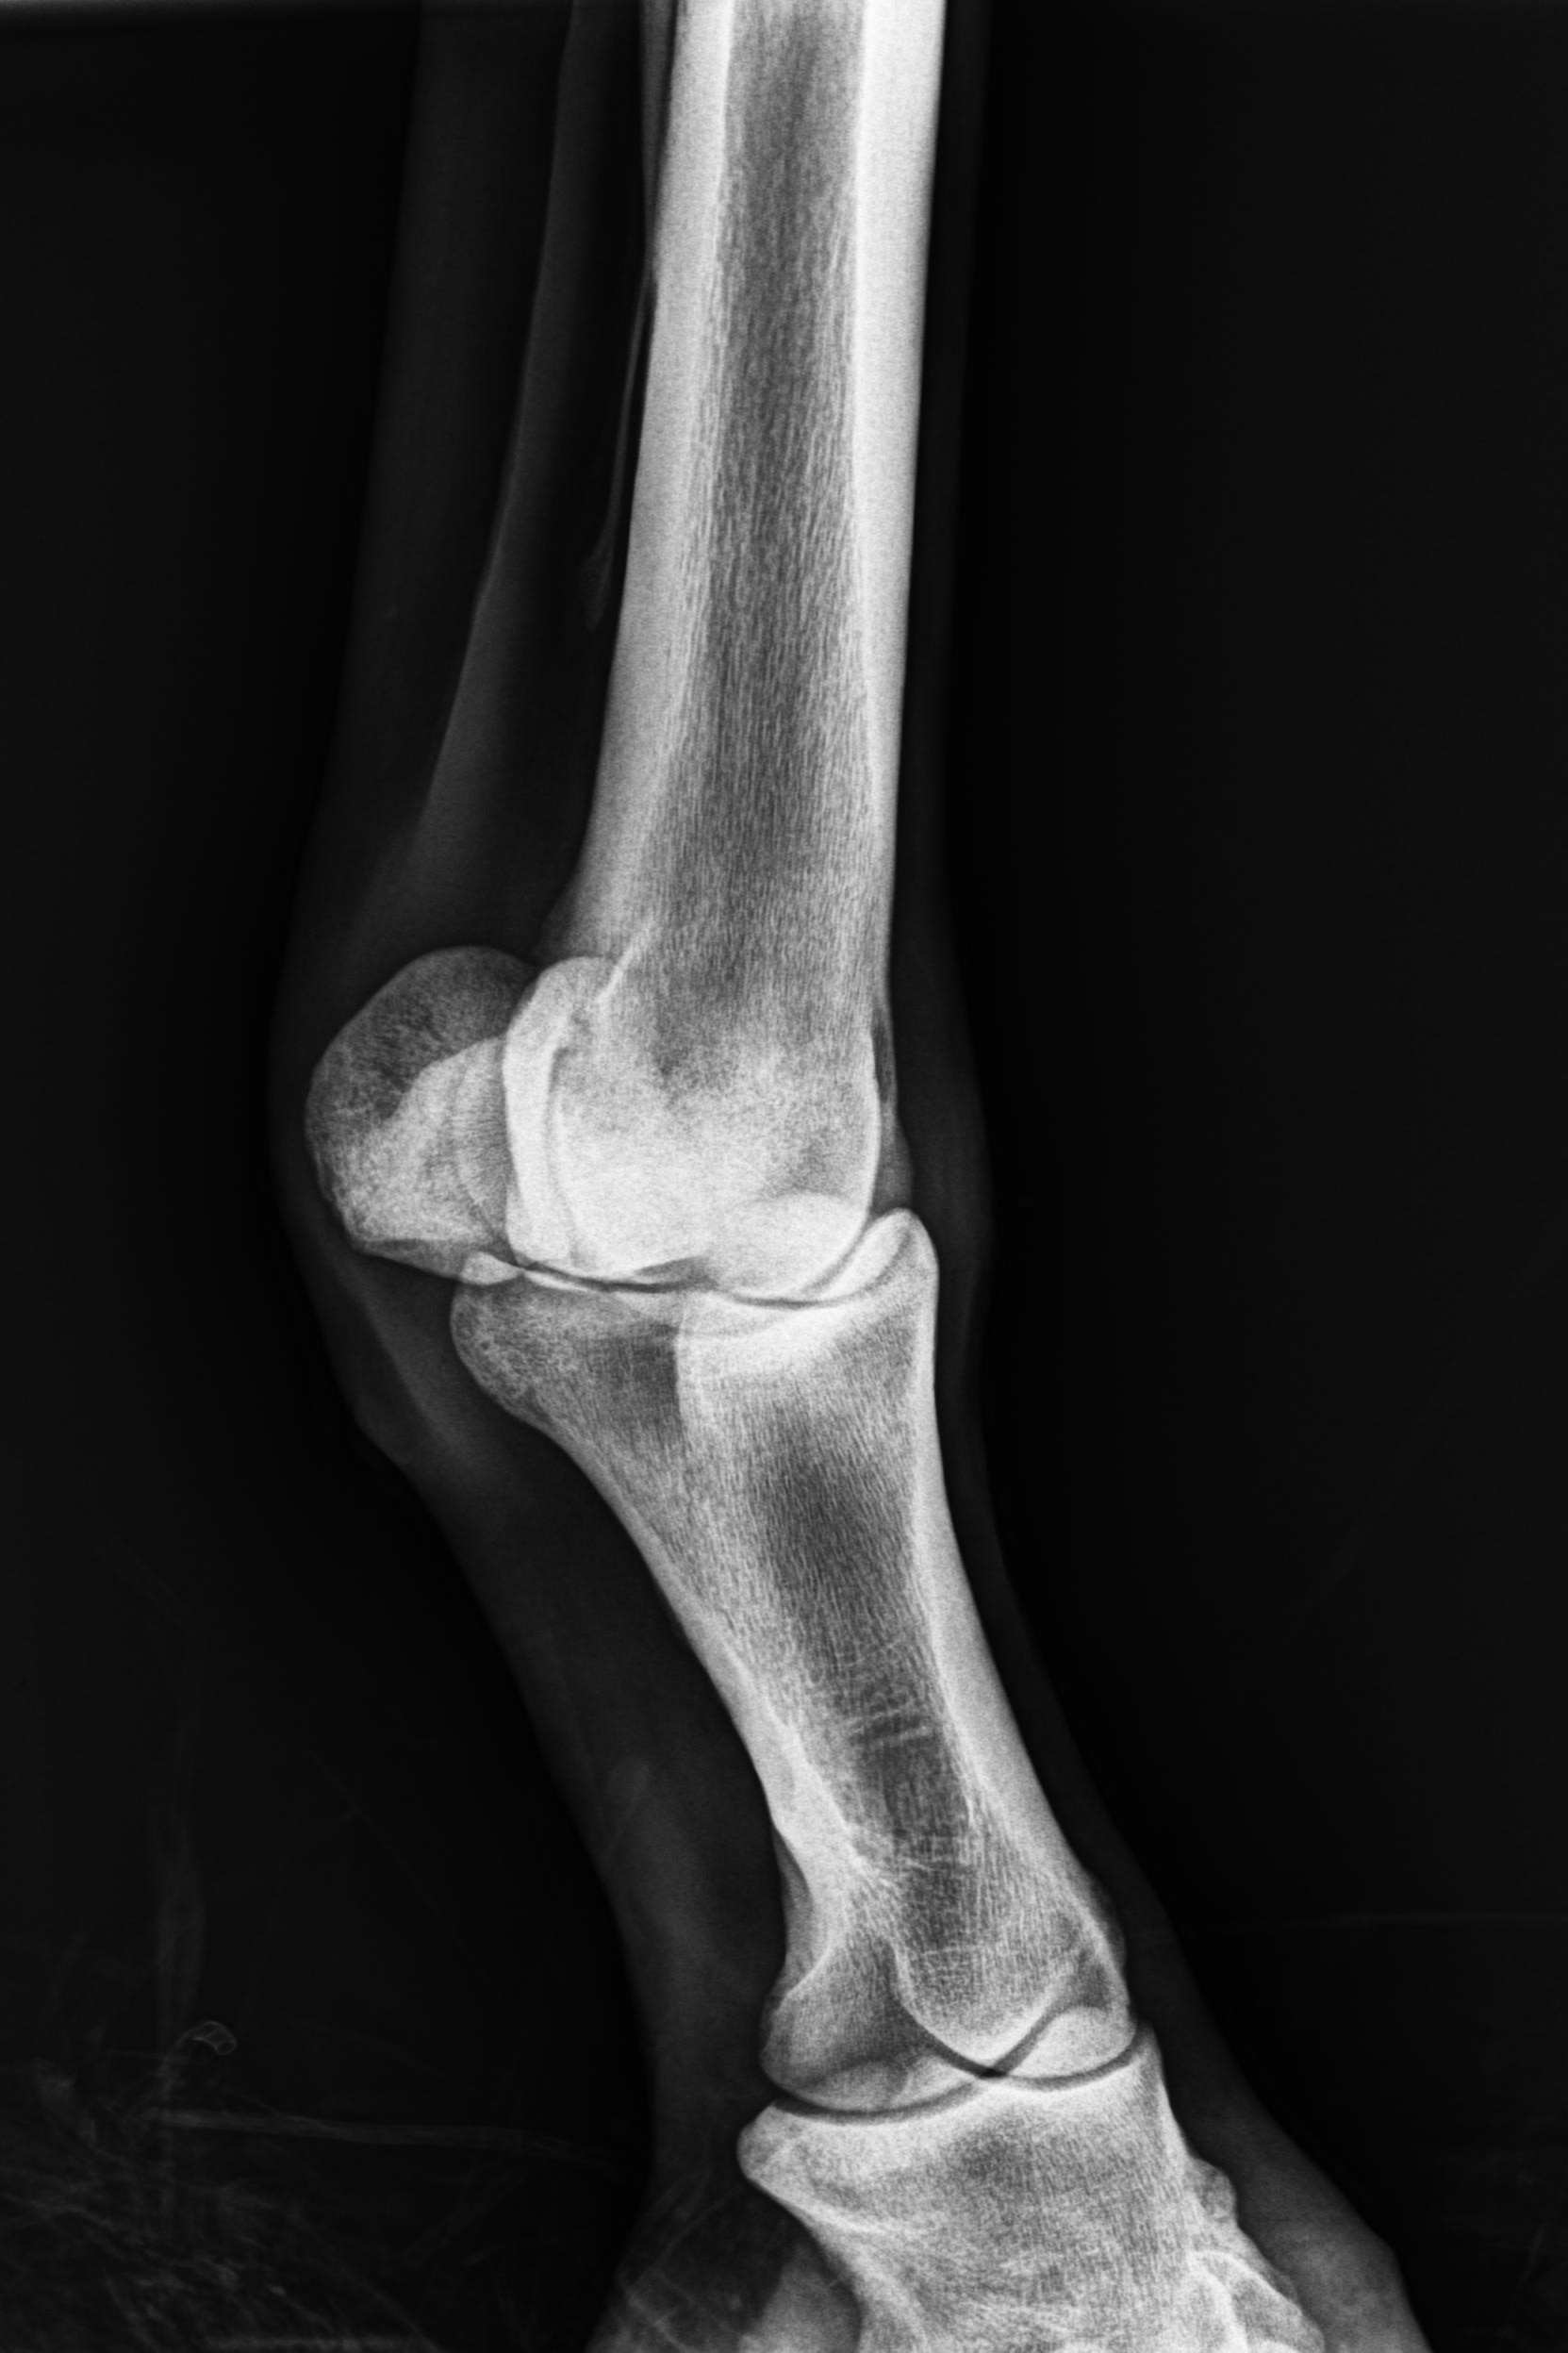

そんな状況の中、1月9日にレントゲン検査を受けると「左前肢外側の種子骨のボーンシスト」が原因と判明しましたので、サラブレッドオークションへ出品とさせていただきます。現状のままでは競走馬としてのデビューは難しいかも知れません。皆様には現状をご理解いただき、事前に獣医検査を受ける等、ご納得をいただいた上でのご検討、ご入札をお願いし、現状渡しのノークレーム、ノーリターンでお願いいたします。

セールの後からお預かりして来ましたが、レントゲン検査を受けて獣医から「このまま調教を進めたら骨折するリスクが大きい」との所見でした。競走馬は勿論ですが、現状のままでは乗馬としても厳しいと思います。(Team百馬力・原翼氏)